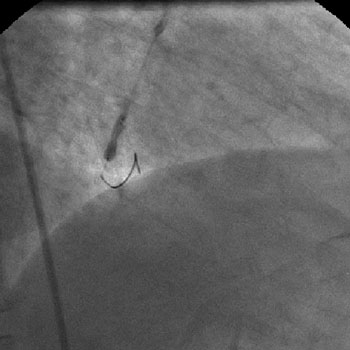

3) LAD: Ostial CTO ( Figure 2) with collaterals from RCA and LCX (Figure 3).

The left system was engaged with XB 3.5 guiding catheter through the femoral route. With the help of a 1.1x1.5mm CTO balloon, we directed a Shinobi guidewire towards the ostial LAD lesion (Figure 4). After making sure that the guidewire was pointing towards the CTO with its tip at the CTO lesion, we used the torquer to gently twirl the guidewire without forcing or overly manipulating it and allowed the guidewire to find its own way through the CTO by patiently twirling it at the lesion site. Within a few minutes, the guidewire jumped through the CTO lesion (Figure 5) and then through the lesion with the help of the CTO balloon (Figure 6). The path was first confirmed by engaging the RCA from the radial approach and injecting dye into the RCA (Figure 7). The CTO was then predilated with a 2.0x30mm Sapphire balloon (Figure 8 and Figure 9) and stented it with a 3.0x36mm DES (Figure 10 and Figure 11). Later the RCA was engaged with a JR 3.5 guiding catheter. A Cougar guidewire crossed the RCA lesion that was directly stented with a 3.0x13mm BMS (Figure 12 and Figure 13).